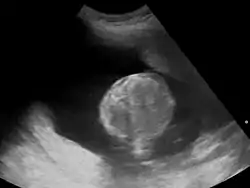

![]() الاستسقاء السلوي بالموجات فوق الصوتية الاستسقاء السلوي بالموجات فوق الصوتية | |

عن طريق التصوير بالموجات فوق الصوتية: مشعر السائل السلوي > 25 سم، يليها فحوصات أخرى مثل: بزل السائل الأمنيوسي، اختبارات سكري الحوامل، تحليل النمط النووي للجنين (karyotyping) و اختبارات أخرى لصحة الجنين.[7]